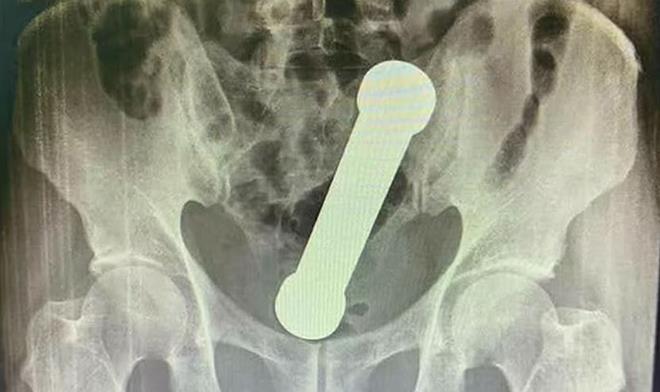

Quả tạ 2 kg mắc kẹt trong trực tràng người đàn ông khiến bác sĩ choáng váng

Các bác sĩ phải dùng tay để lấy quả tạ nặng 2 kg, dài 20 cm ra khỏi trực tràng người đàn ông, dị vật được bệnh nhân sử dụng để tìm khoái cảm tình dục.